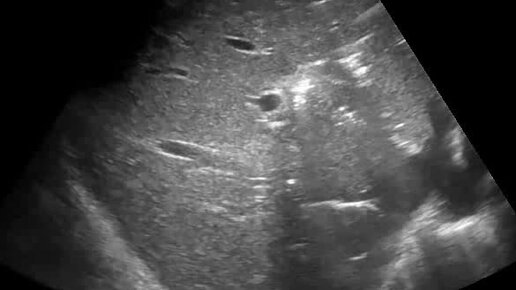

Ультразвуковые находки от врача УЗД Зорина Я.П.